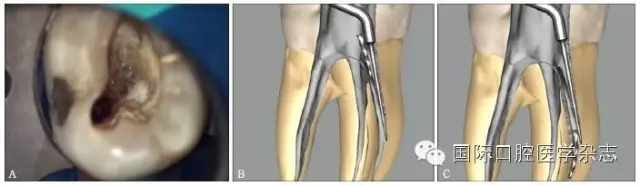

根管預(yù)備是根管治療最重要的步驟之一,預(yù)備根管后可以有效沖洗根管,清除根管內(nèi)微生物,為根管充填提供空間。由于種種原因,例如擴(kuò)孔鉆、根管銼、拔髓針等根管器械在操作時(shí),如果超過器械的極限強(qiáng)度,或者材料強(qiáng)度不能耐受正常的臨床加載力時(shí),器械就可能會(huì)分離在根管中(圖1)。

圖 1 根管內(nèi)分離的各種器械